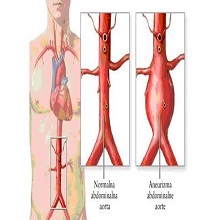

Анеуризма аорте је локализовано, трајно проширење крвног суда од најмање 50% ширег пречника, у односу на крвни суд здраве особе истог пола и старости, а која садржи сва три слоја зида. |